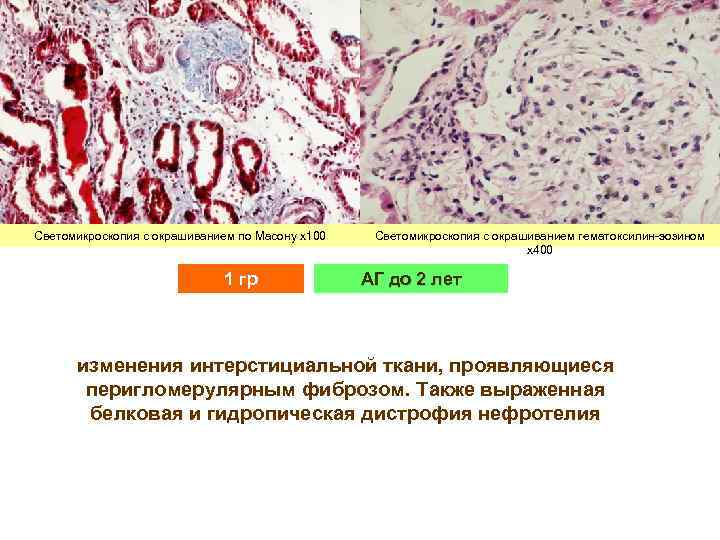

Светомикроскопия с окрашиванием по Масону х100 1 гр Светомикроскопия с окрашиванием гематоксилин-эозином х400 АГ до 2 лет изменения интерстициальной ткани, проявляющиеся перигломерулярным фиброзом. Также выраженная белковая и гидропическая дистрофия нефротелия

Светомикроскопия с окрашиванием по Масону х100 1 гр Светомикроскопия с окрашиванием гематоксилин-эозином х400 АГ до 2 лет изменения интерстициальной ткани, проявляющиеся перигломерулярным фиброзом. Также выраженная белковая и гидропическая дистрофия нефротелия